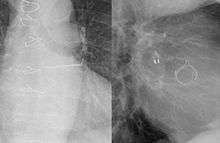

![]() The left atrial appendage is the windsock-like structure shown to originate from the left atrium (three o'clock). | |